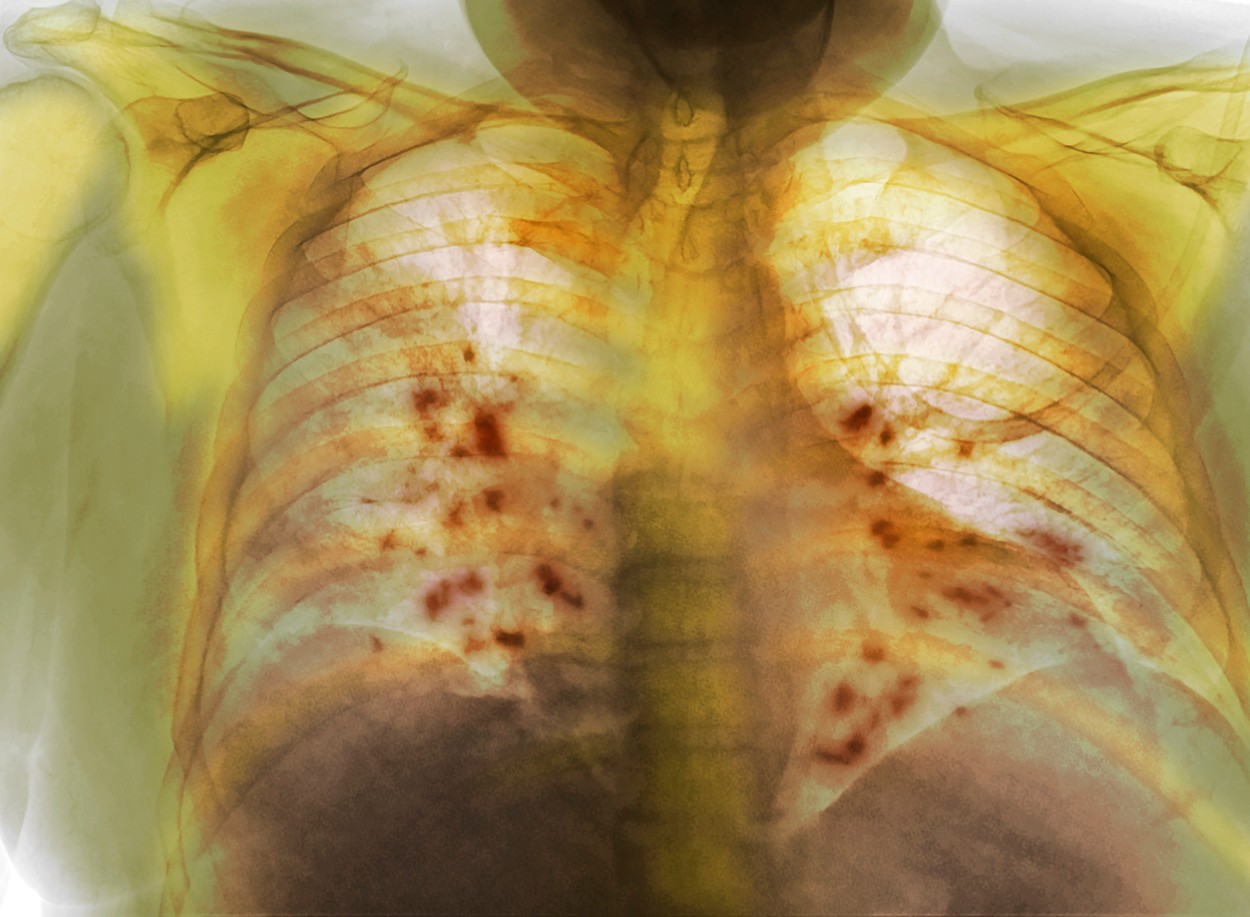

Pluća posle kovida; Foto: DR P. MARAZZI / Sciencephoto / Profimedia Pluća posle kovida; Foto: DR P. MARAZZI / Sciencephoto / Profimedia Pluća posle kovida; Foto: DR P. MARAZZI / Sciencephoto / Profimedia Zaključci naučnika nakon ispitivanja ožiljaka na plućima od kovida autor: N1 Magazin 15. dec. 2021. 13:59 > 15. dec. 2021. 14:00 0 Podeli vest: Odavno znamo kakvu štetu težak oblik kovida-19 može da nanese plućima, ali tačni razlozi tih promena još se proučavaju. Studijom, koja bi mogla da pomogne boljem lečenju zaraženih koronavirusom, naučnici u Nemačkoj pokazali su da je kovid-19 često praćen teškim ožiljcima na plućnom tkivu. Podeli vest: Oglas Tim naučnika na čelu s Leifom-Erikom Sanderom u bolnici „Charite“ u Berlinu kaže da zastoj pluća možda nije prouzrokovao samim umnožanjem virusa, već odgovorom imunskog sistema tela, između ostalog.Njihovi zaključci, objavljeni u naučnom časopisu „Cell“, ukazuju na to da virus Sars-CoV-2 prouzrokuje da „ćelije čistači“ imunskog sistema pokrenu stvaranje ožiljaka koji na kraju oštećuju pluća.Takva reakcija imunskog sistema znači da pacijenti sa kovidom-19 moraju da budu veoma dugo na kiseoniku ili čak moraju da budu priključeni na mehaničku ventilaciju.Ako pacijent ima težak oblik kovida-19, postoji velika mogućnost da će razviti akutni respiratorni distres sindrom (ARDS).U svojoj studiji naučnici predvođeni Sanderom došli su do zaključka da plućno tkivo pacijenata postaje ožiljno promenjeno, zadebljano i neelastično.Vrlo slični procesi se javljaju u idiopatskoj plućnoj fibrozi, ranije neizlečivom obliku ožiljnih promena na plućima.Naučnici su prvo pod mikroskopom gledali plućno tkivo pacijenata preminulih od posledica kovida-19 i pronašli su karakteristične oblike teške fibroze.„Gotovo svi pogođeni pacijenti imali su opsežno oštećenje tkiva. Većina alveola je uništena, a zidovi alveola su pokazali visoki stepen zadebljanja. Takođe smo svuda pronašli naslage kolagena, glavne komponente ožiljnog tkiva“, rekao je Piter Bur sa Instituta za patologiju na Univerzitetu RWTH Ahenu.Zastoje pluća po pravilu se ne razvija u dve do tri nedelje nakon pojave prvih simptoma, objasnio je Sander.„To ukazuje da zastoj pluća nije prouzrokovan nekontrolisanom replikacijom virusa, već sekundarnim odgovorima domaćina, uključujući one koji uključuju imunski sistem“.Tim je zatim pregledao imunske ćelije u plućima teško bolesnih ili preminulih pacijenata sa kovidom-19.Otkrili su da se u plućima obolelih pacijenata nakupljaju makrofagi – imunske ćelije koje uklanjaju patogene i ćelijski otpad, ali učestvuju i u lečenju rana.U teškim slučajevima kovida-19, čini se da dolaze u kontakt sa određenim ćelijama vezivnog tkiva i tada se snažno razmnožavaju i stvaraju velike količine kolagena.Naknadna istraživanja na ćelijskim kulturama ukazivala su na to da virus Sars-CoV-2 izaziva pogrešnu reakciju makrofaga. Virus gripa, sa druge strane, to ne izaziva.„Naši podaci zbog toga pokazuju paralele između kovida-19 i idiopatske plućne fibroze“, rekao je Antoine-Emanuel Saliba sa nemačkog istraživačkog instituta Helmholc i dodao:„To može da objasni zašto su neki od faktora rizika za kovid-19 takođe faktori rizika za idiopatsku plućnu fibrozu. Ti faktori obuhvataju neka zdravstvena stanja, pušenje, muški pol i starije od 60 godina“.Za razliku od idiopatske plućne fibroze, čiji je uzrok nepoznat, ožiljci kod pacijenata sa kovidom-19 mogu da se povuku, makar delimično, kažu naučnici. Tokom oporavka od bolesti, zadebljanja i ožiljci se barem delimično povuku.Detaljnije istraživanje procesa regresije ožiljaka na tkivu moglo bi da doprinese razvoju mogućih lečenja za obe bolesti ili sprečavanju nastanka ožiljaka od samog početka.***Bonus video: Dr Gojković Bukarica razbija zablude o "farmako mafiji" video-cdn src="https://best-vod.umn.cdn.united.cloud/stream?asset=razbijamozabludeovakcinacijiljiljanagojkovicbukarica-novas-worldwide&stream=hp3500&t=0&player=m3u8v&sp=novas&u=novas&p=n0v43!23t001" video-id="2605826"]***Pratite nas i na društvenim mrežama:FacebookTwitterInstagram istraživanje kovid pluća Pratite nas na društvenim mrežama: Koje je tvoje mišljenje o ovoj temi? Učestvuj u diskusiji ili pročitaj komentare Budite prvi koji će ostaviti komentar Pošalji komentar Pročitaj komentare (0)